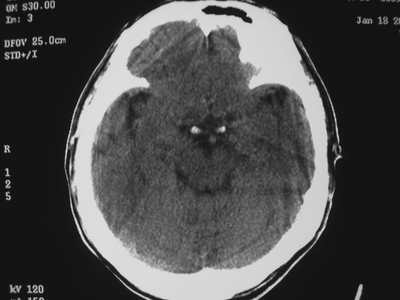

以下是引用卜一在2007-1-19 15:29:00的发言:[br]治疗前:1月14日右侧额叶皮质下低密度影,而治疗后:1月18日右侧阴影消失,新近出现左侧额叶侧脑室前角旁大片状低密度影,边缘模糊。支持—双侧额叶后部缺血性脑梗塞。